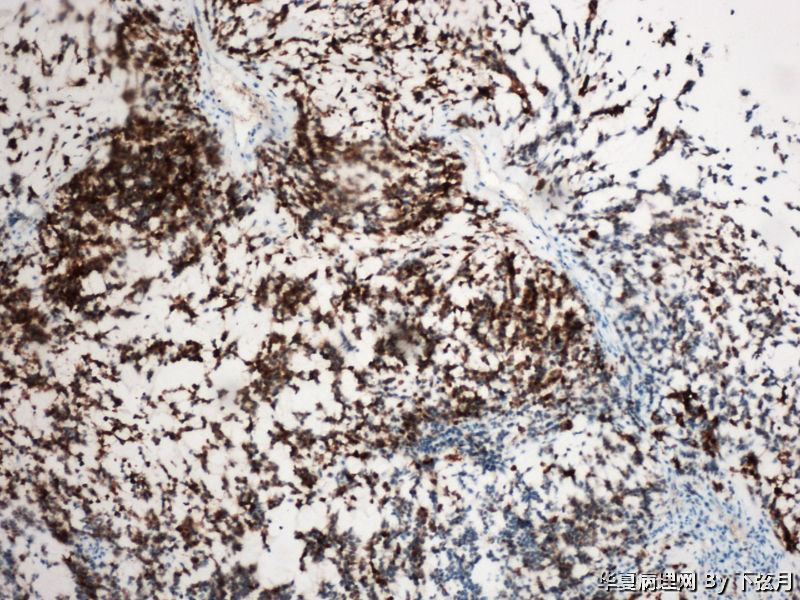

描述:S100 100倍

左侧颞叶及胼胝体膝部占位图16

名称:图16

描述:S100 200倍

考虑黏液型乳头状室管膜瘤

丰富黏液背景,漂浮乳头状或簇状分布的瘤细胞,免疫组化GFAP,S-100阳性。

从图1可见肿瘤似位于脑皮质外围,有粘液背景,部分如脊索瘤样,倾向于脊索瘤样脑膜瘤。